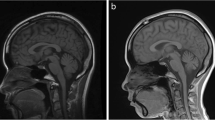

Supratentorial structures are affected, though less prominently. The group has not been clarified genetically or biochemically. An initial proposal for classification [6] is based on two types in which type 1 (PCH-1) associates PCH with spinal anterior horn cell degeneration [14, 33], while type 2 (PCH-2) associates PCH with clinical extrapyramidal involvement and absence of anterior horn degeneration [5–7, 37, 44]. Early detailed neuropathological reports on PCH [9, 10, 26] in retrospect may have been cases of PCH-2, but cannot be matched with the customary classification because of lack of clinical details. Neuropathological finding in PCH-2 [5, 7, 37, 41] is microencephaly with severe cerebellar and ventral pontine hypoplasia. Typical pathological findings are: (1) subtotal loss of ventral pontine neurons and transverse pontine fibers with preservation of long fiber tracts; (2) atrophy and hypoplasia of the cerebellar hemispheres with relative sparing of the vermis and flocculi, variable loss of Purkinje cells and internal granule cells and reduction in folial length; (3) patchy loss of cerebellar dentate neurons, with the remaining dentate neurons grouped in “islands”; (4) loss of neurons in the inferior olivary nucleus with the winding pattern essentially spared; (5) absence of the medullary arcuate nuclei. Findings in PCH-1 are essentially similar, but preservation of spinal anterior horn cells distinguishes PCH-2 from PCH-1 [14]. Microscopic supratentorial findings in PCH-2 are non-specific with neuronal loss in various compartments, including the cerebral cortex, while myelin and myelination remain unaffected. Ultrastructural findings in a single reported neocortical biopsy are progressive neuronal loss in all layers and a peculiar degeneration in neurons in all layers that appear to start with patches of darkened endoplasmic reticulum [5]. Diagnosis during life is based on a combination of findings on MRI (Fig. 1), a profile of clinical neurological deficits that includes severe cognitive delay, swallowing disturbance and chorea/dystonia (less often, spasticity), exclusion of metabolic and chromosomal disorders with a similar MRI pattern and a family history compatible with autosomal recessive inheritance. In typical cases, behavioral and motor development is almost stagnant from the beginning, with onset of chorea/dystonia during the first year and progressive microcephaly [7, 44]. Differential diagnosis requires exclusion of glycosylation disorders, especially congenital disorder of glycosylation type 1A (CDG1A) [2, 21, 23] and Muscle-Eye-Brain disease [16, 29], sequelae of extreme prematurity [28] and chromosomal disorders [4]. Overlapping neuropathological features exist between PCH-2 and olivopontocerebellar hypoplasia (OPCH), a more severe disorder with an essentially similar combination of hypoplasia and degeneration affecting the hindbrain [3, 11, 18, 35]. Autosomal recessive inheritance in OPCH is suggested by its recurrence pattern in families. Clinical findings are variable, but include such indicators of prenatal onset as polyhydramnios and contractures. Its main structural features are severe cerebellar hypoplasia with emphasis on the hemispheres, absence of neurons in the ventral pons, subtotal absence of cerebellar dentate nuclei, diminished or absent olivary winding and absence of spinal anterior horn involvement. In a recent PCH classification, the original types 1 and 2 have remained identical, while olivopontocerebellar hypoplasia has become type 4, PCH-4 [36]. Type 3, with optic atrophy as its main distinguishing clinical feature [38], has not been studied neuropathologically yet, while type 5 until now is represented by a single family. The number of papers addressing the neuropathology of PCH-2 with sufficient clinical detail to support a type 2 classification is limited [5, 37, 41] and results of immunohistochemistry have not been reported yet. The aim of the present report is to provide a range of pathological findings based on a series of six autopsies with ages at death varying between 15 months and 22 years and to provide an update on neurodegenerative features using more specific staining techniques. Special attention is given to variability in cerebellar degeneration, degenerative changes in pons and lower brainstem and the types of astroglial and microglial reaction. Three patients (no. 4, 5, 6) originate from an area with a high degree of intermarriage and are related by genealogy. A case of olivopontocerebellar hypoplasia (PCH-4) is included for comparison of its neuropathology to PCH-2.

The cerebellar hemispheres are severely affected in all. On macroscopic examination, all major lobes are reduced in width and dorsoventrally flattened. Size was best preserved in the transverse plane. This asymmetric diminution in size and the relative sparing of the vermis lend the cerebella a butterfly or batwing aspect (Fig. 1b). Four of the six cerebella (cases 2, 4–6) are sectioned perpendicular to the folia with the line of the sectioning running from the culmen to the posterior pole. These sections include the flocculus. In two cases (1, 3), transverse sections of hemispheres and vermis are prepared. Low magnification (Fig. 3) shows the diminished size of the cerebellar hemispheres, folial shortening and diminished number of folial branches compared to a control (Fig. 3a, b). In the most affected case (Fig. 3g, h), no branches are seen at all, while in a less affected case folial branches are reduced to two or less (Fig. 3e, f). The other cerebella displayed regular folial branching (Fig. 3c, d), though less in quantity than the control specimen (Fig. 3a, b).